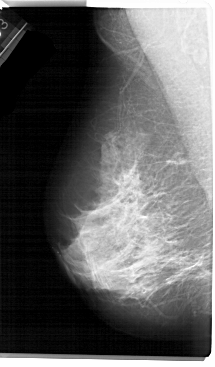

A_1305_1.RIGHT_MLO

RIGHT_MLO LINES 5491 PIXELS_PER_LINE 3241 BITS_PER_PIXEL 12 RESOLUTION 43.5 OVERLAY